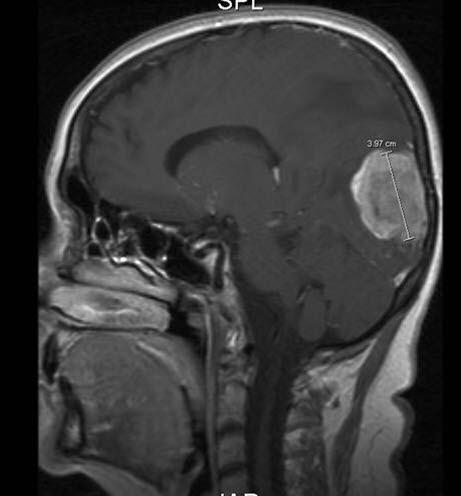

MR er den mest sensitive undersøkelsen såvel til påvisning av små metastaser som får å påvise andre sykdommer i hjernen. Ved CT av hjernen med kontrast finnes multiple hjernemetastaser hos ca. 50%, ved MR-scanning hos ca. 75%.